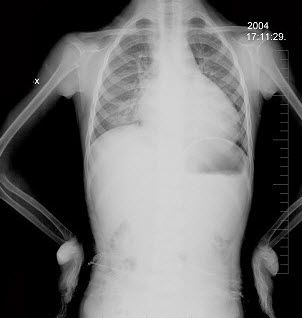

75、单项选择题

出生1天的早产儿,呼吸窘迫,结合图片,最可能的诊断是()

A.湿肺

B.肺气肿

C.肋骨骨折

D.肺气肿

E.气胸